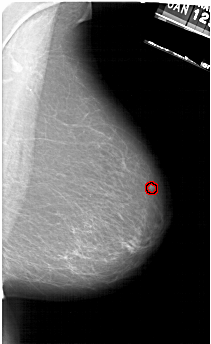

A_1161_1.LEFT_CC

LEFT_CC LINES 6301 PIXELS_PER_LINE 3661 BITS_PER_PIXEL 12 RESOLUTION 43.5 NON_OVERLAY

FILE: A_1161_1.RIGHT_MLO.OVERLAY

TOTAL_ABNORMALITIES 1

ABNORMALITY 1

LESION_TYPE MASS SHAPE IRREGULAR MARGINS ILL_DEFINED

ASSESSMENT 4

SUBTLETY 1

PATHOLOGY MALIGNANT

TOTAL_OUTLINES 1

BOUNDARY